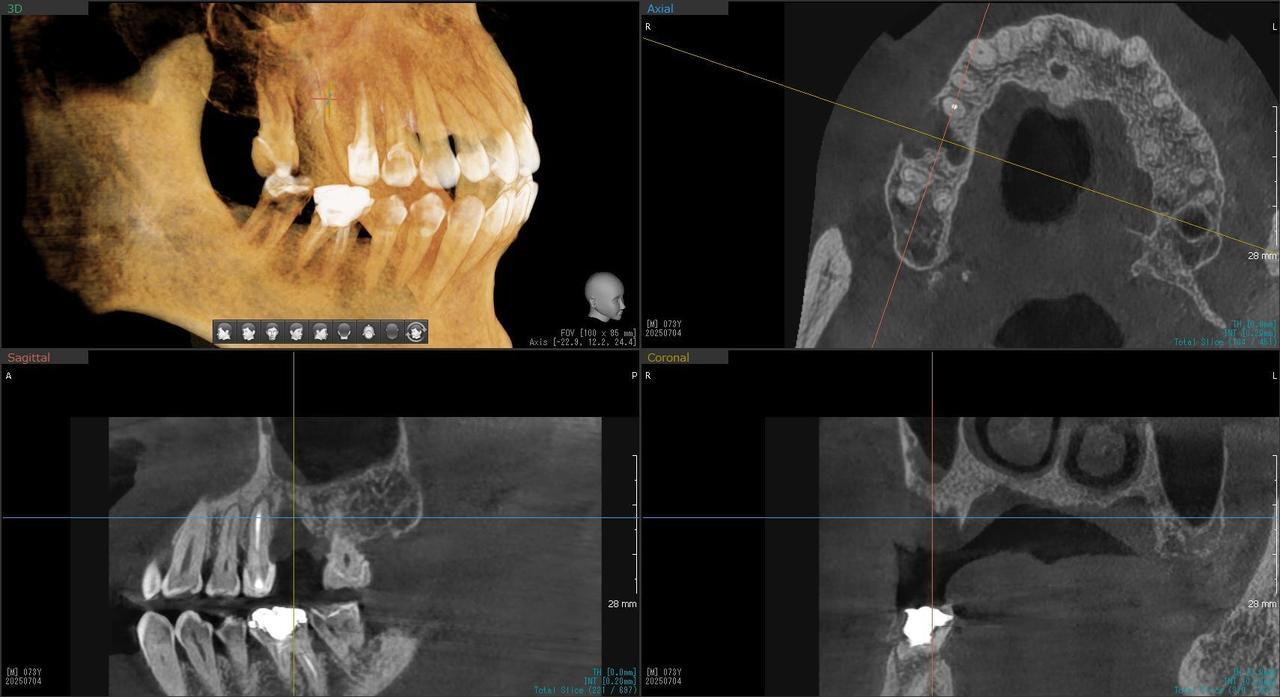

3.左上5の頬・舌側の大幅な骨欠損と上顎既存骨3mmまでの骨欠損がおこった症例に対しておこなったインプラント治療

Before

枚方市のインプラントの症例

After

I・K 様 女性 40代

症状としては、左上5の歯根破折を起こしていたため、排膿と自発痛をみとめた。それにともなう骨の大きな欠損。

治療法としては、炎症が強くたったためと、炎症による頬側側歯肉の退縮を認めていたために、まず、抜歯を行い上顎洞内及び歯抜した周囲組織の回復を試みた。その後、患者様がインプラント治療を希望したため、薄い上顎骨に対しては、グラフトレスサイナスリフト、骨欠損部には、人口骨補填を行い、頬側歯肉が退縮していることを改善するために、1回法でリーリングアバットメントを装着して、アバットメントの上に歯肉が覆うようにして、歯肉のボリューム回復を行った。2か月後、インプラントが骨と結合していることを確認して、光学印象を行い、2週間後にアバットメントとジルコニアクラウンを装着した。

治療結果としては、大幅な骨欠損があったが、グラフトレスサイナスリフトと骨欠損部に人工骨を補填して、抜歯した穴が自然に治る状態にしたことで、2か月半という短い期間での治療を完了することができた。(仮に、GBRや通常のサイナスリフトでの治療を行っていたら、最低でも1年は、かかってくる治療であると考える。)また、今回は、即時荷重を避け、1回法での治療を行ったことで、噛めない期間ができてしまったが、1回法で行ったことにより、歯肉のボリュームが増して、ブラッシングがしやすい口腔内環境にすることができた。低侵襲で、短時間で、治療を終えることができ、また、審美性・機能性の回復も行えたことができた。

治療の期間・回数:約2.5か月、6回

治療の価格:368,500円(税込)

治療費の内訳:インプラント基本料(フィックスチャー及び手術費用、投薬費用、レントゲン費用、インプラント上部費用(アバットメントおよびジルコニアクラウンの費用用)330000円(税込み)。オプション費用グラフトレスサイナスリフト費用プラス人工骨費用 38500円(税込み

治療のリスクや副作用:手術後に、痛みや腫れ、出血、合併症などを引き起こす可能性があります。噛む感覚がご自身の歯と異なる場合があります。見た目がご自身の歯と異なる場合があります。手術後にメインテナンスを継続しないと、インプラントが抜け落ちる可能性があります。